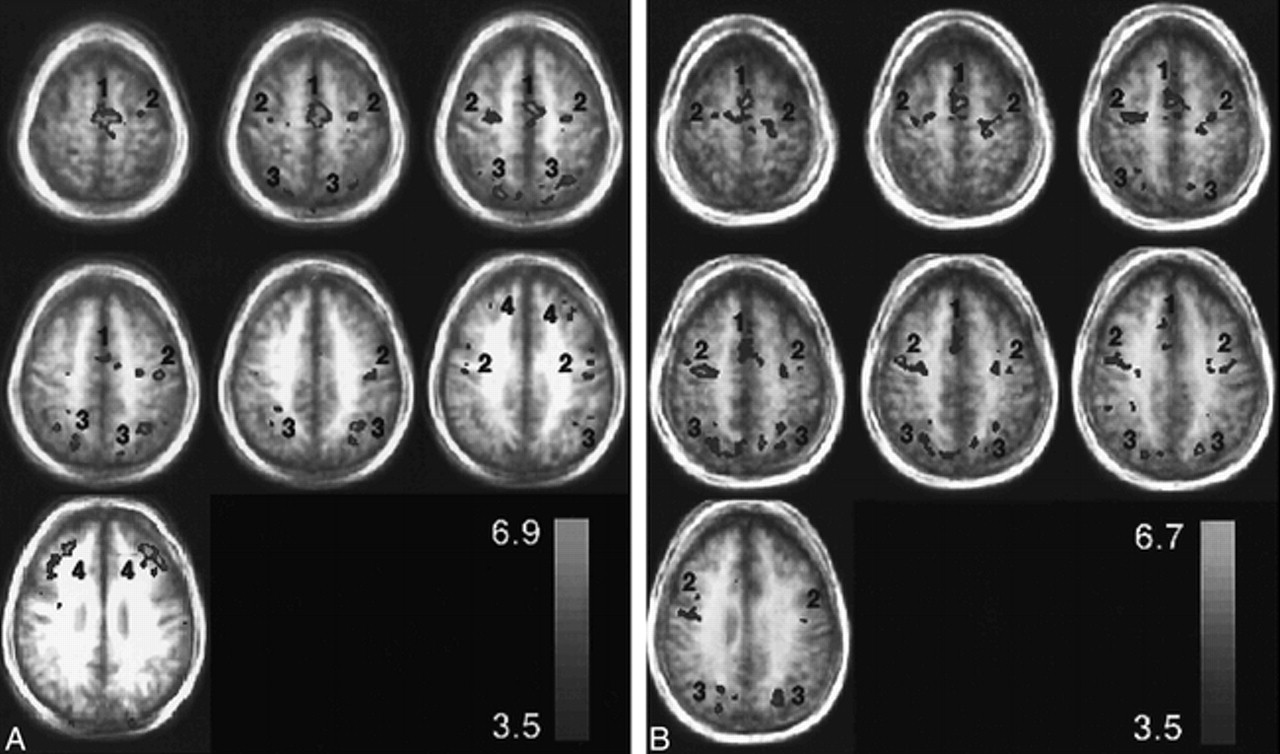

Representative group axial activation maps (t > 3.5) for the visually guided saccade paradigm through the SEF (1), FEF (2), IPS (3), and PFC (4). The activation is displayed as a hot iron color scale (bottom right) where red is the lowest t threshold and yellow is the peak t value. The activation is displayed over group structural images to show the degree of blurring from biological anatomic variation. A relates to patients with pAD and B to control volunteers.

Figure 1 shows activation maps in seven axial planes for the pAD and control groups (panels A and B, respectively). The distributions of activation for the pAD and control groups are summarized in Figure 2 (panels A and B, respectively) as plots of a percentage activation volume in right and left hemispheres for each of the four sites of activation (SEF, FEF, IPS, PFC). This percentage distribution parameter effectively normalizes the amount of activation, independent of the chosen t threshold, to allow the patterns in the two groups to be compared. LRs for both groups are presented in Table 3.

The mean Talairach coordinates, Brodmann areas, and peak percent signal change of the four regions of activation (FEF, SEF, IPS, PFC) are presented in Table 1 for each hemisphere of the individual data for the cognitively able elderly group. The equivalent results for the patients with pAD are presented in Table 2. The variation in coordinates determined for each epicenter of activation of each individual was less than 15 mm for both groups. The group activation maps also gave activation epicenter coordinates (not shown) within the same variance as averaging individual participant coordinates for each group (Tables 1 and 2). There was little difference in the SD of the coordinates across the individual participants of both groups for the four areas. A wider spread of activation around the PFC epicenter was observed on the activation map of the pAD group than on the activation map of the control volunteers, as shown in Figure 1. The signal change for BOLD contrast of approximately 1% did not vary between hemispheres of individual participants or between the two groups (Tables 1 and 2). The measurements of total parenchymal volumes of the cerebral hemispheres were not significantly different between the two groups (control group, 869 ± 101 cm3; pAD group, 831 ± 113 cm3). Similarly, no differences were found for the smaller regions, such as the occipitoparietal region.